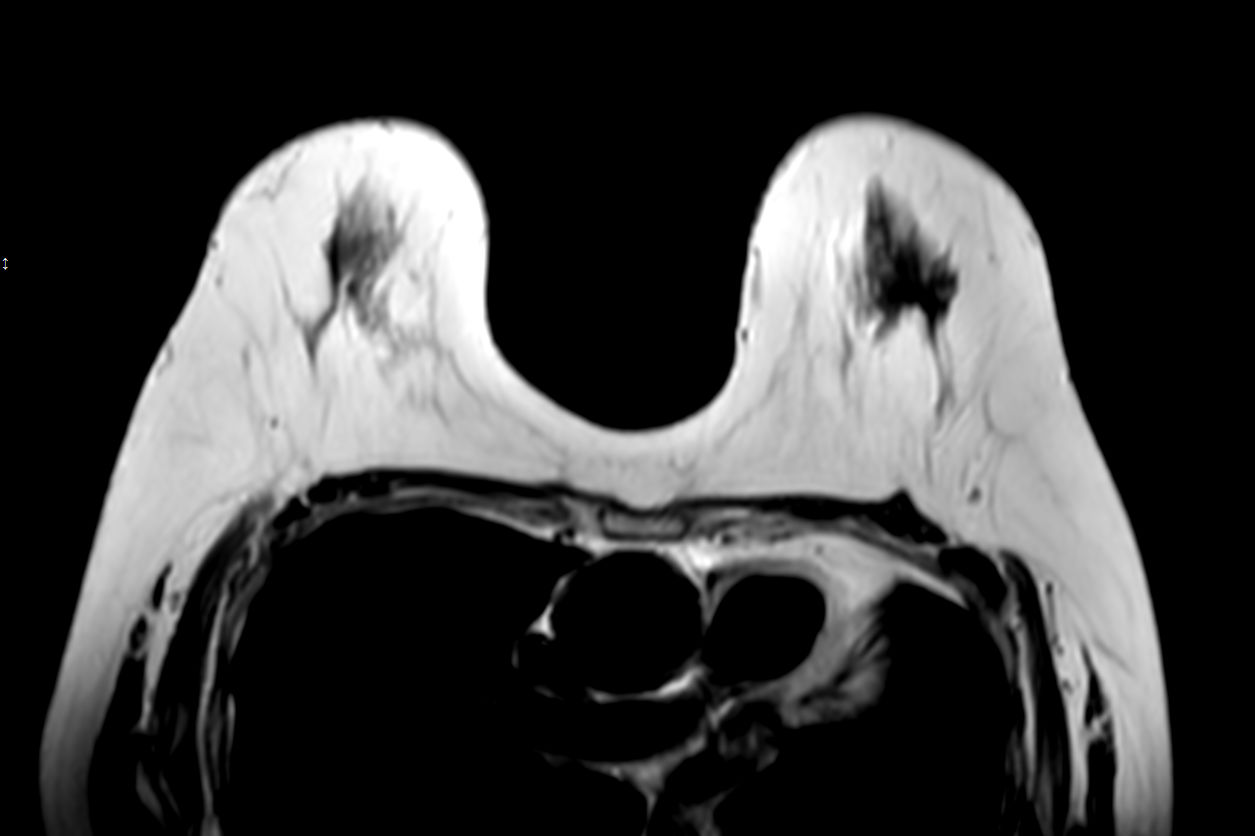

T1w TSECompressed SENSE

-